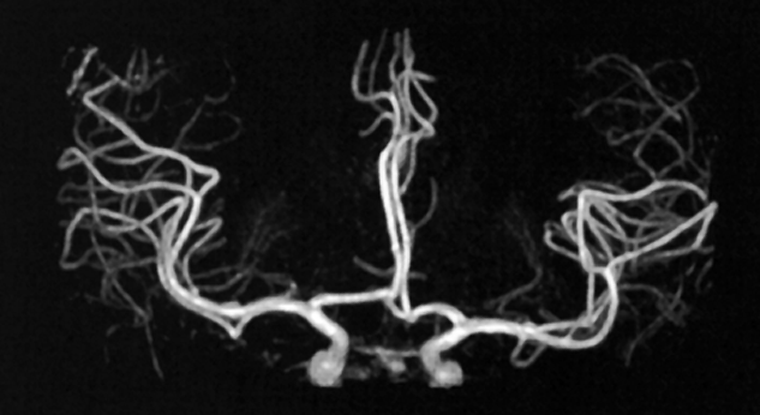

Figura 14-17:

Brain angiogram using TONE and MTC